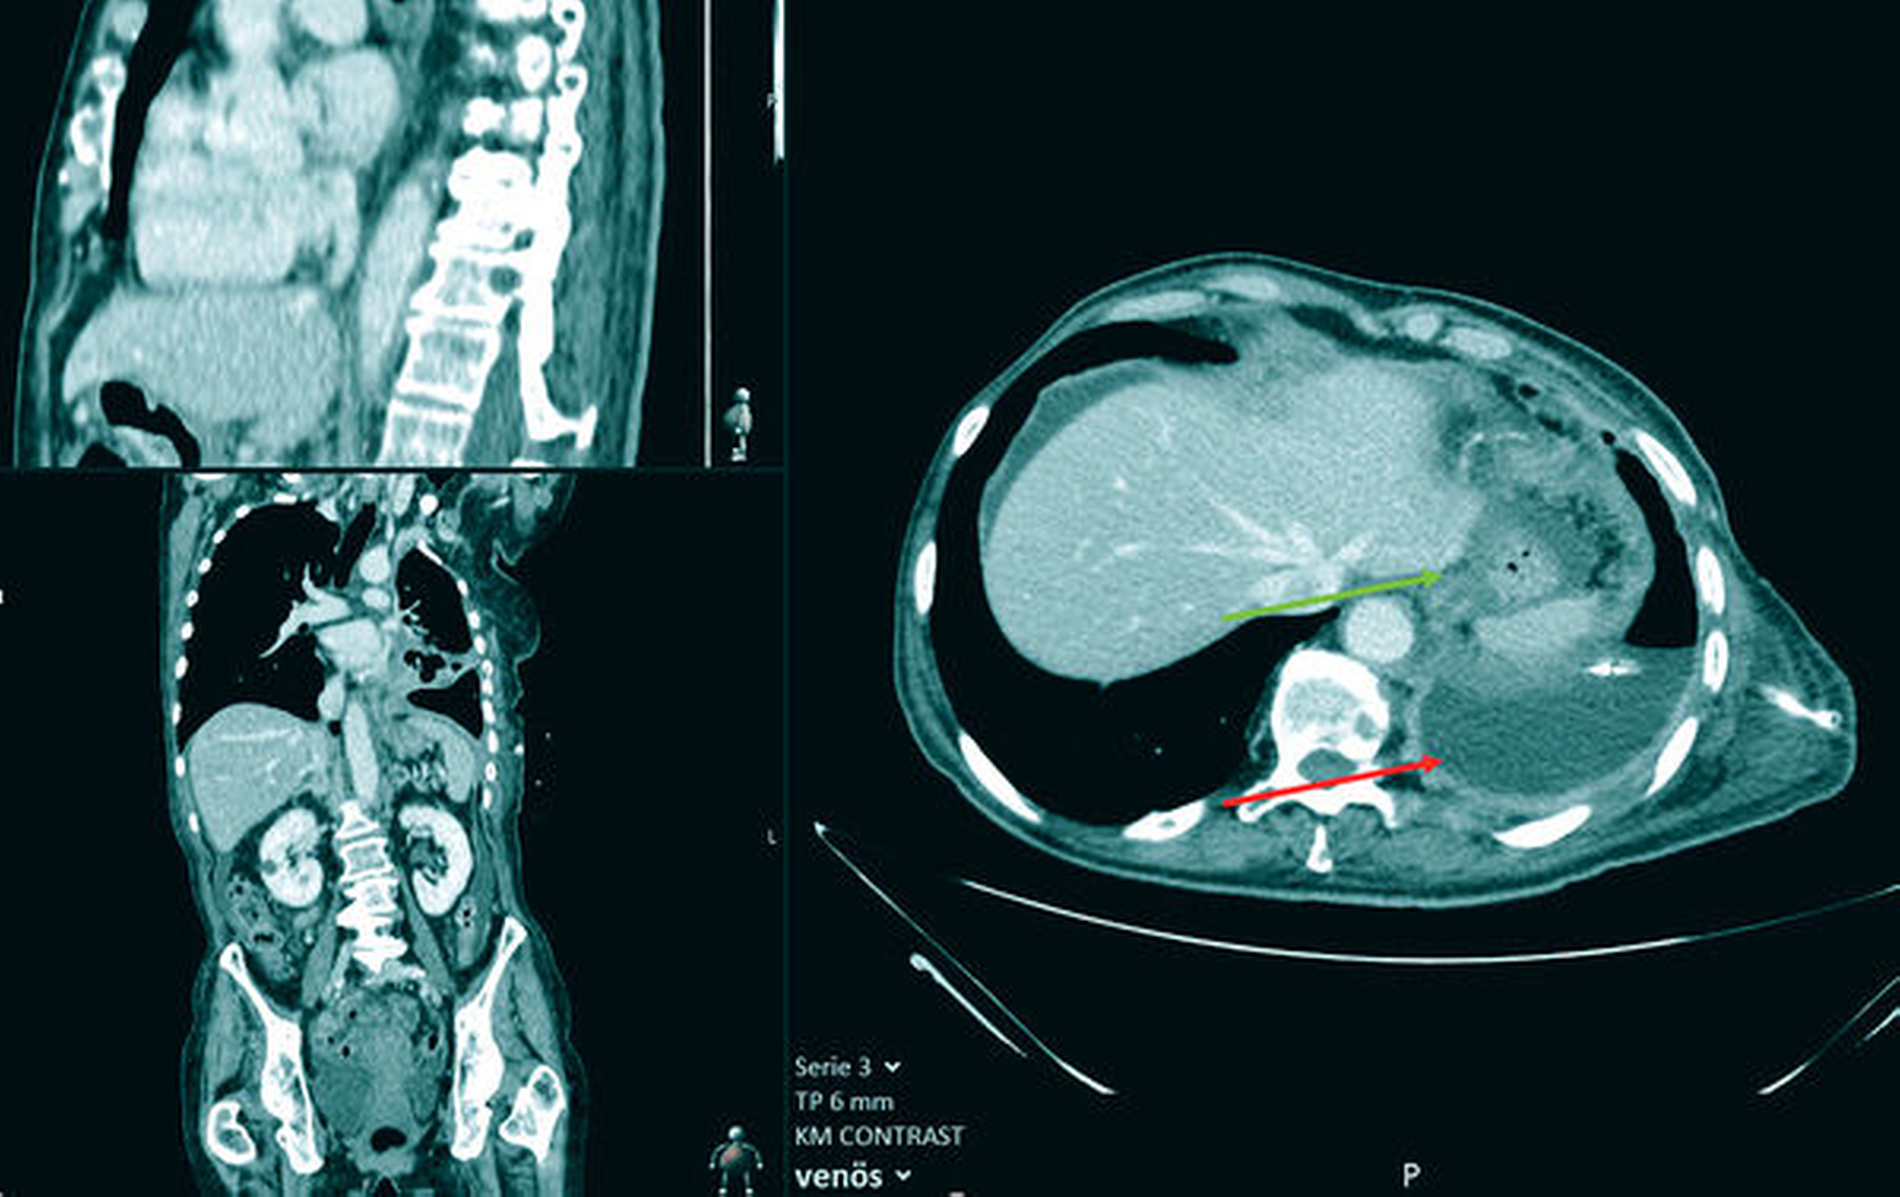

Trotz Radio- und Chemotherapie in den Jahren 2019 und 2020 imponierten in den nachfolgenden CT- und MRT-Untersuchungen weitere Metastasen in der Leber, in der rechten Niere sowie im Achsenskelett und in der Schädelkalotte als disseminierte osteolytische Knochenmetastasen (Abbildung 3). Weitere Therapiemaßnahmen lehnte die Patientin ab; sie wurde auf eigenen Wunsch in die Häuslichkeit entlassen.